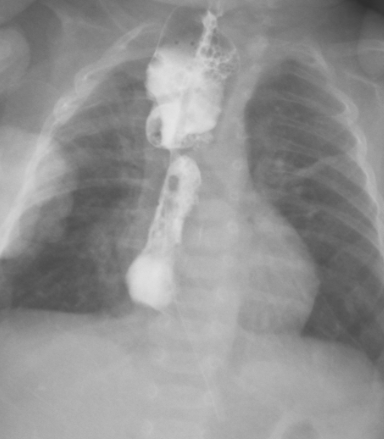

图 3 造影提示吻合口漏持续存在

给予万古霉素抗感染治疗。9.5 腹部彩超:胃内可见少量内容物,余肠管肠腔萎瘪,走形迂曲;腹腔未见明显肠套叠、肠梗阻及阑尾炎征象。9.13 食管造影:食道闭锁术后改变,吻合口漏。贲门位置抬高,建议随诊肺炎。2021-09-28 造影检查: 食管造影:食道闭锁术后改变,吻合口漏,较前稍好转。贲门位置抬高,建议随诊;肺炎;先天性心脏病。磁共振检查 (1T 以上不含 1T): 颅脑 (磁共振功能成像, 平扫):早产儿脑,左侧侧脑室后角室管膜下局灶性脑损伤,小脑幕缘硬膜下少量出血。

入院诊断:入院后完善术前检查,给予箱内吸氧(3L/min),头孢他啶抗感染,维生素 K1 预防维生素 K 缺乏性出血,禁饮食、胃肠减压、补液等对症支持治疗。监测血压、血糖、心电、血氧。确诊食管闭锁。于 2021 年 8 月 19 日行经胸膜外食管吻合术,术后出现吻合口漏,感染指标上升。2021.09.05 根据引流液培养缓症链球菌,药敏结果选用头孢哌酮舒巴坦及万福霉素抗感染治疗,感染指标有所下降,但一直未正常,反复出现喂养不耐受,贫血等症状。先后多次因贫血输红悬液治疗。09.14 停用万古霉素抗感染。2021.09.24,取痰培养,2021.09.25 经验升级抗菌素为美罗培南抗感染。09.26 日行 mNGS 检测。09.27mNGS 结果回报提示为粘质沙雷氏菌,大肠埃希菌,缓症链球菌,产气克雷伯氏菌。同时痰培养结果回报。痰培养结果提示未大肠埃希菌但是几乎全部耐药,仅替加环素敏感。同时提示还有 CMV 感染。考虑多重感染可能性大,继续应用对粘质沙雷氏菌,大肠埃希菌,缓症链球菌,产气克雷伯氏菌等病原均有作用的美罗培南抗感染,同时停用对耳肾毒性较大的万古霉素抗感染。患儿精神状况好转,感染指标逐渐下降至正常,喂养耐受,肠内营养增加,贫血改善。2021.10.09 血常规及 c 反应蛋白正常,感染控制。2021.10.19 复查造影提示吻合口漏愈合(图 4)。10 月 22 日因食管狭窄再次行食管狭窄扩张治疗,术后恢复顺利,10.28 达到临床治愈出院。